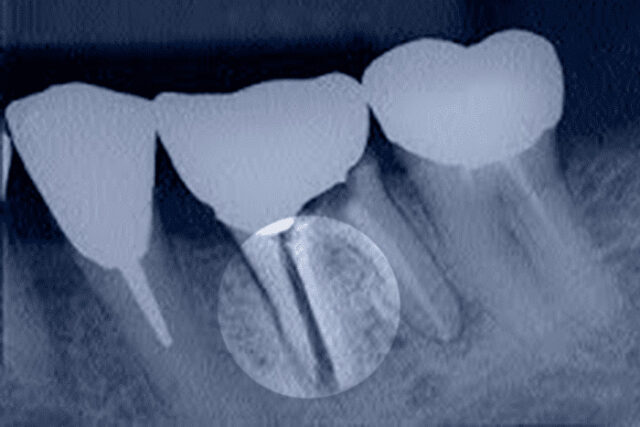

- при одномоментной имплантации, когда на место поврежденного зуба сразу устанавливают титановый винт;